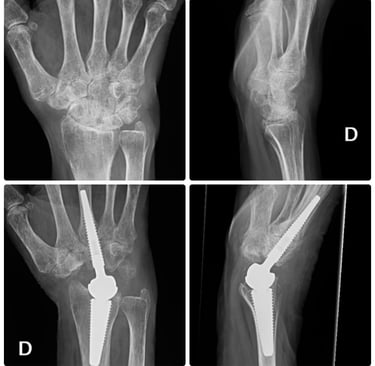

Prótesis de muñeca y dedos.

Prótesis para rizartrosis.

Osteotomías correctoras con planificación 3D

Transferencias nerviosas y tendinosas

Artrodesis totales o parciales

Especialistas en cirugía prótesica

Tratamiento de secuelas y casos complejos

Prótesis de tobillo y artrodesis avanzada

Soluciones definitivas para artrosis avanzada

✔ Artrosis tibioastragalina

✔ Artrosis subastragalina

✔ Hallux rigidus severo

➡ Prótesis total de tobillo

➡ Artrodesis anatómica

➡ Recuperación funcional orientada al paciente activo